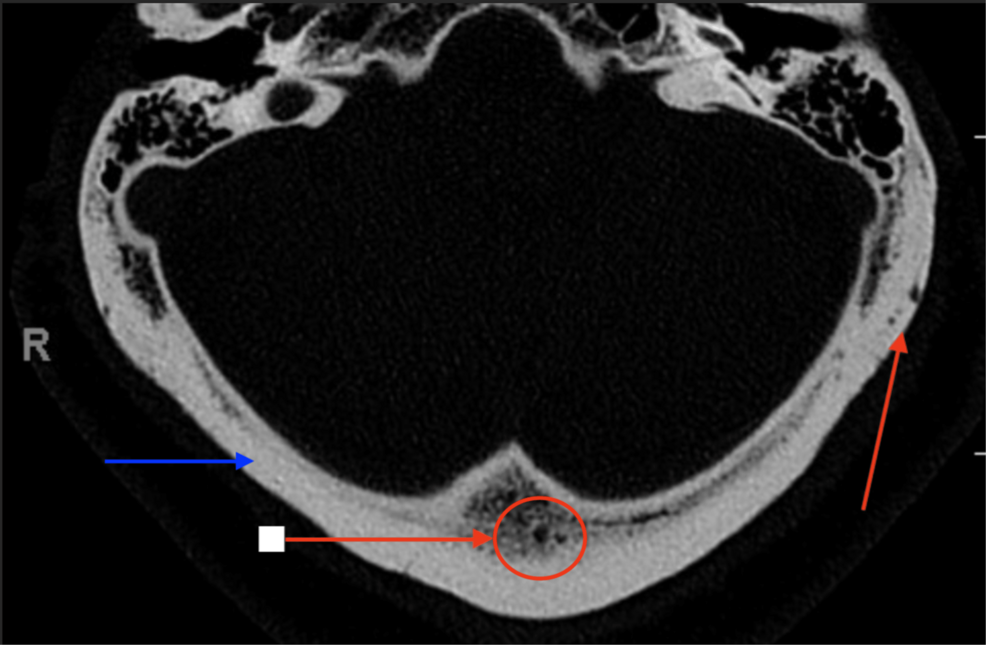

Unraveling Diagnostic Challenges in Lytic Bone Lesions: A Case Study and Broader Implications A recent case report published this week details a complex diagnostic journey involving a patient presenting with ... Read More